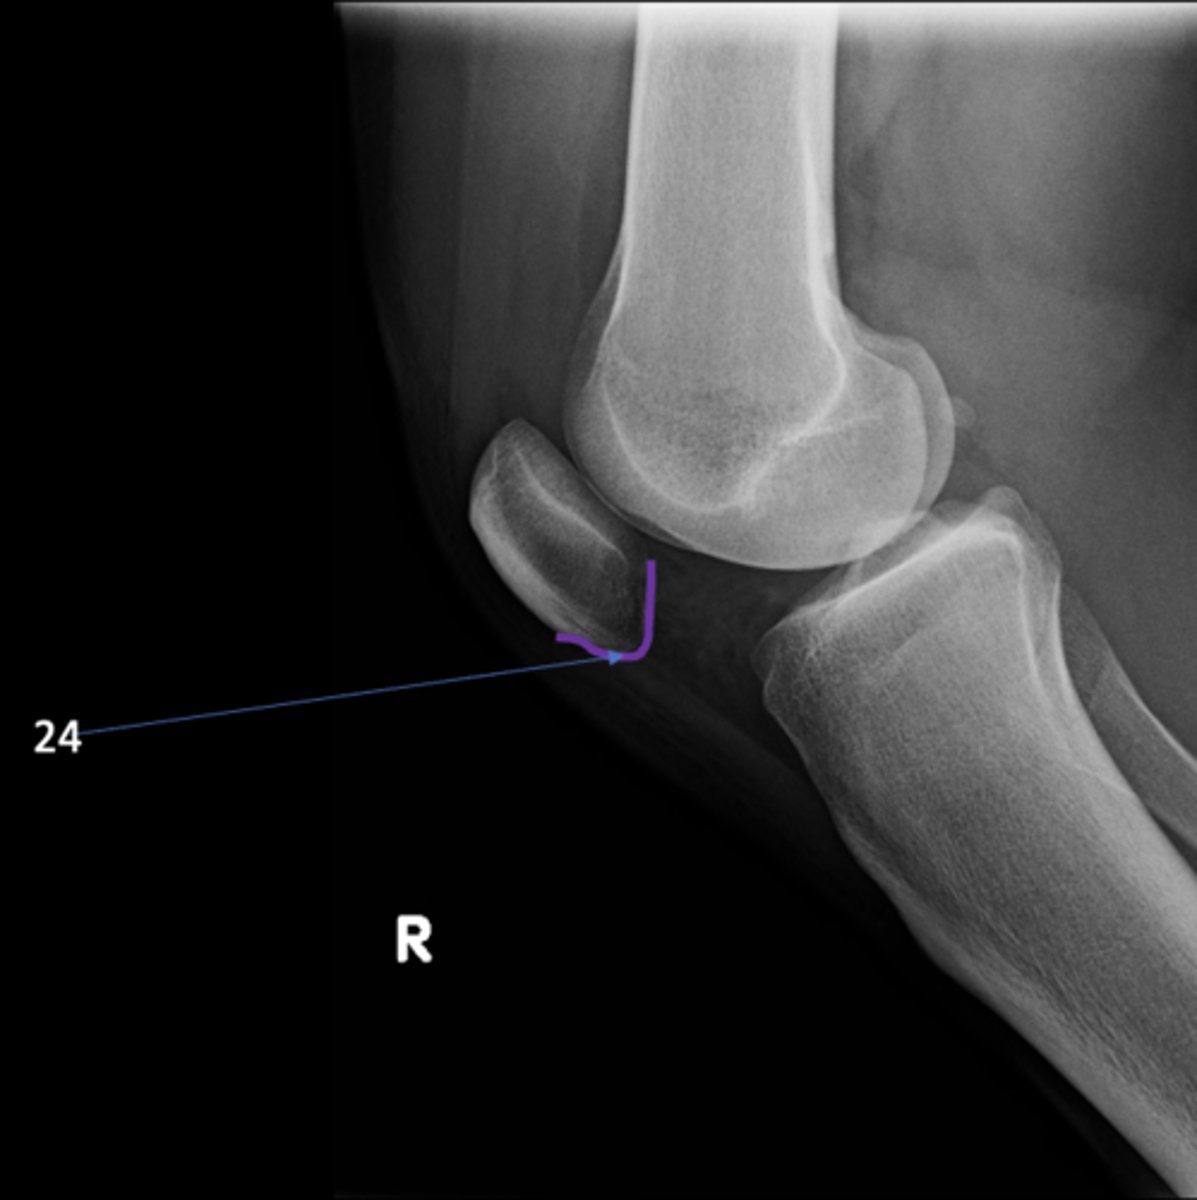

67

New cards

Right lateral knee

View?

72

Apex of patella

ID 24

<p>ID 24</p>

73

75

Apex of fibular head

ID 28

<p>ID 28</p>